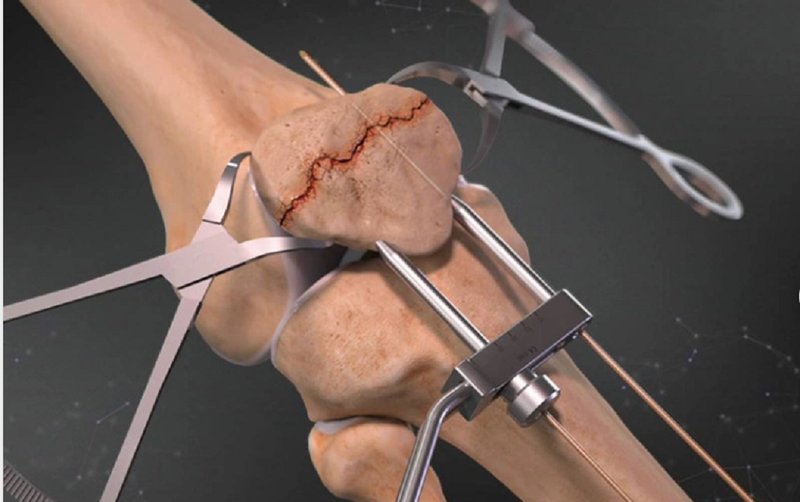

Được áp dụng trong những trường hợp xương bánh chè gãy với độ di lệch lớn hơn 4mm hoặc trật khớp trên 2mm và khiến cho động tác duỗi gối bị hạn chế. Mục tiêu của phẫu thuật là thu nhỏ diện tích bề mặt khớp, đảm bảo ổn định cấu trúc xương gân đầu gối và hỗ trợ mở rộng phạm vi chuyển động để phục hồi khả năng kéo dài của đầu gối.

Phương pháp phẫu thuật kết hợp xương bánh chè cụ thể sẽ được quyết định dựa trên tình trạng của xương bánh chè bị gãy, ví dụ như: